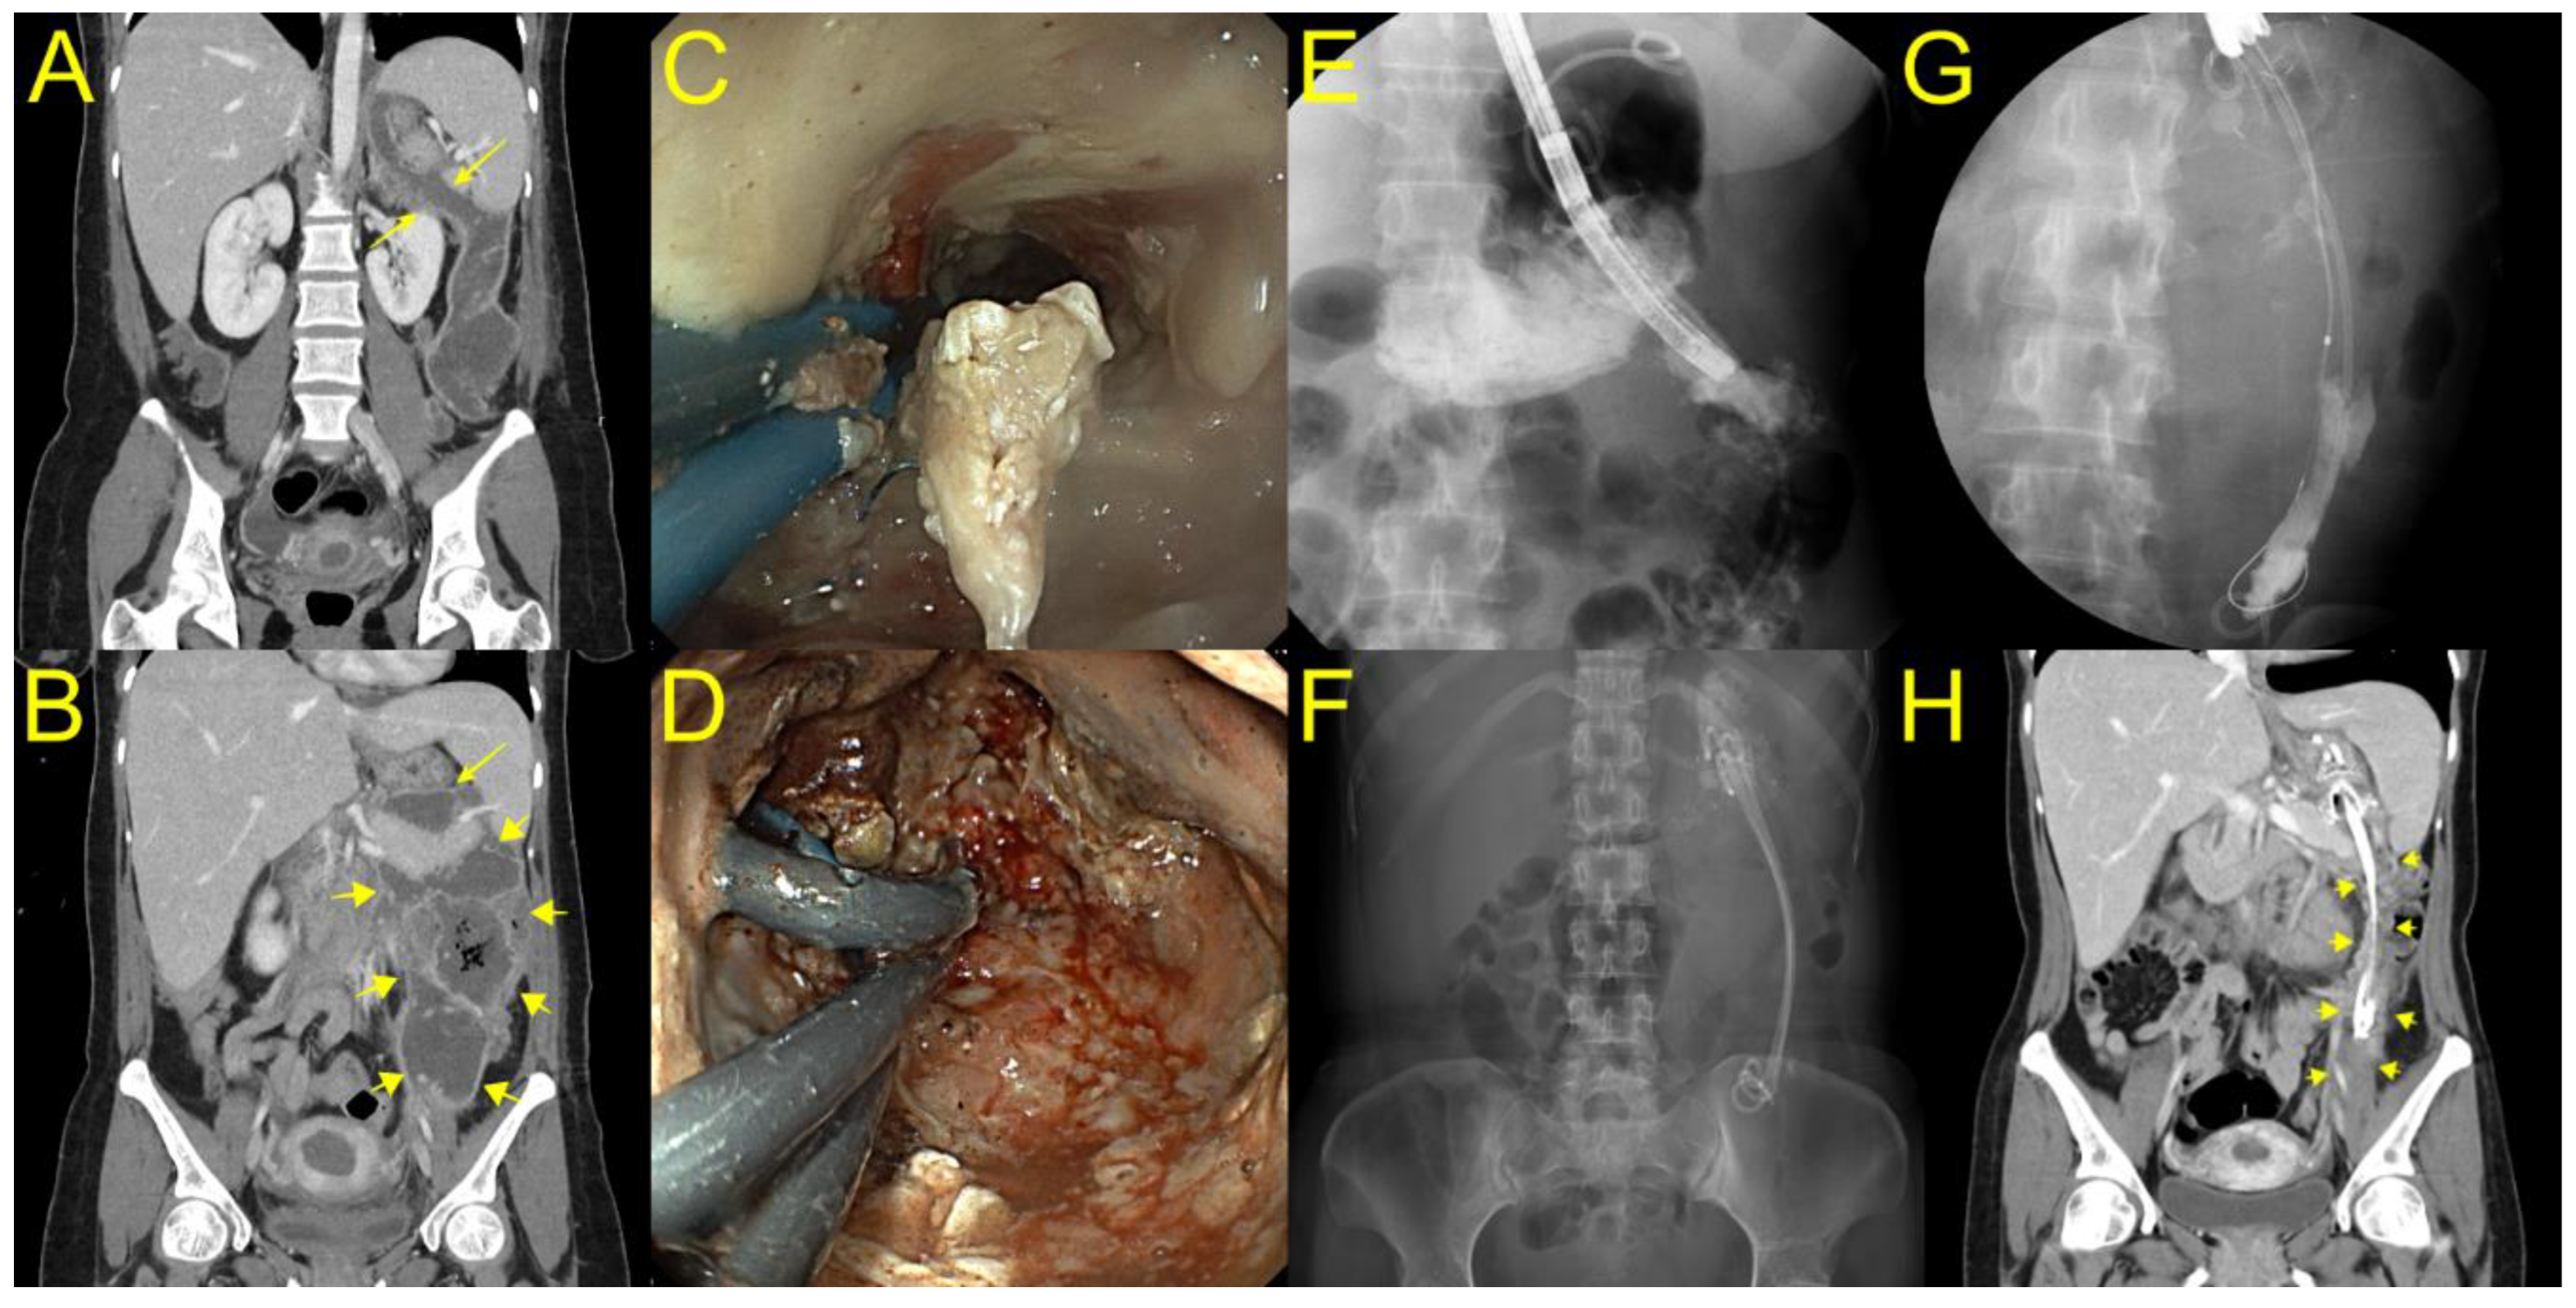

Figure 2. Placement of long plastic stents to the deep portion of walled off necrosis (WON) after direct endoscopic necrosectomy (DEN) for endoscopic treatment of laterally extended WON (yellow arrow) (A). (B) Computed tomography showing a huge WON extended to the left pelvic cavity communicating to a small portion of the necrotic cavity concatenated with the stomach through the narrow neck (yellow arrow) portion. (C) A gastroscope was inserted into the proximal portion of WON through a lumen-apposing metal stent (LAMS), and we found a luminal stricture of the neck portion of WON. (D) Balloon dilatation (yellow arrow) was performed for deep insertion of an endoscope to the laterally extended WON. (E,F) The cavity was lavaged with normal saline, and necrotic debris was progressively removed with snare and grasping forceps. (G) After DEN, three plastic stents with double pigtail configuration were fixed in place through the LAMS to the deep portion of WON until the next session of DEN. (H) After 16 DEN sessions, where the long plastic stents remained in the deep portion of WON, the patient recovered with complete WON resolution (yellow arrow).